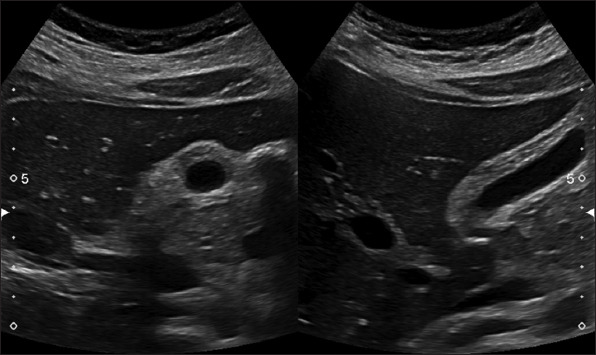

Results: A total of 31 case reports (level of clinical evidence: IV) of AAC related to COVID-19 were included. The mean age of patients was 64.7 ± 14.8 years, with a male-to-female ratio of 2.1:1. Major clinical presentations included fever 18 (58.0%), abdominal pain 16 (51.6%), and cough 6 (19.3%). Hypertension 17 (54.8%), diabetes mellitus 5 (16.1%), and cardiac disease 5 (16.1%) were among the common comorbid conditions. COVID-19 pneumonia was encountered before, after, or concurrently with AAC in 17 (54.8%), 10 (32.2%), and 4 (12.9%) patients, respectively. Coagulopathy was noted in 9 (29.0%) patients. Imaging studies for AAC included computed tomography scan and ultrasonography in 21 (67.7%) and 8 (25.8%) cases, respectively. Based on the Tokyo Guidelines 2018 criteria for severity, 22 (70.9%) had grade II and 9 (29.0%) patients had grade I cholecystitis. Treatment included surgical intervention in 17 (54.8%), conservative management alone in 8 (25.8%), and percutaneous transhepatic gallbladder drainage in 6 (19.3%) patients. Clinical recovery was achieved in 29 (93.5%) patients. Gallbladder perforation was encountered as a sequela in 4 (12.9%) patients. The mortality rate in patients with AAC following COVID-19 was 6.5%.